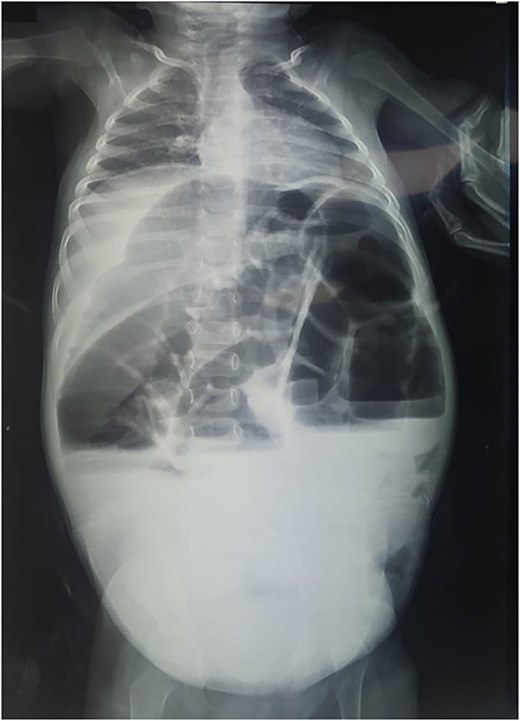

Reviewing the medical record of the patient, she underwent variable blood tests that were negative mostly except for ionogram disturbances due to malnutrition and dehydration. An abdominal X-ray was performed at each episode of hospitalization, that revealed intestinal-type hydroaeric levels and gastric stasis (Fig. 1) then a digestive fibroscopy with multiple biopsis as well as eosogastroduodenal transit were run out suggesting gastritis. A barium index (Fig. 2) was also performed on his last hospitalization suggesting a small bowel obstruction which also appeared on the Enteroscan (Fig. 3).

X-ray image showing intestinal-type hydroaeric levels and gastric stasis.